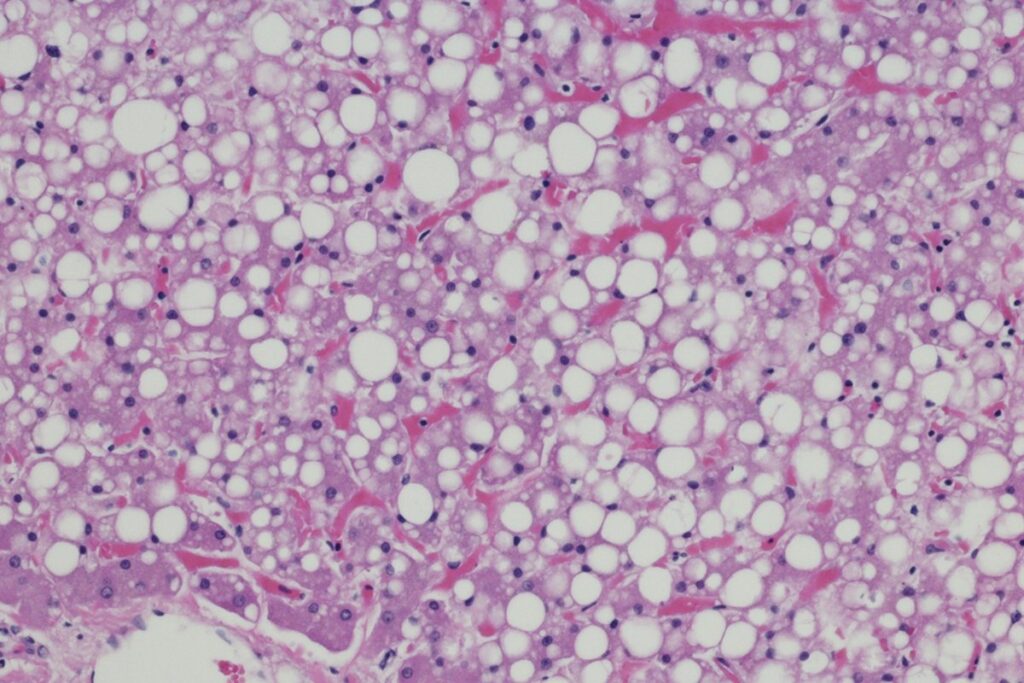

Uma condição cada vez mais comum, a esteatose hepática, conhecida como gordura no fígado, é uma doença de estilo de vida. Desencadeado por obesidade, má alimentação, sedentarismo e excesso de álcool, o acúmulo excessivo de gordura nas células hepáticas é preocupante e pode causar problemas sérios de saúde, como cirrose e até câncer.